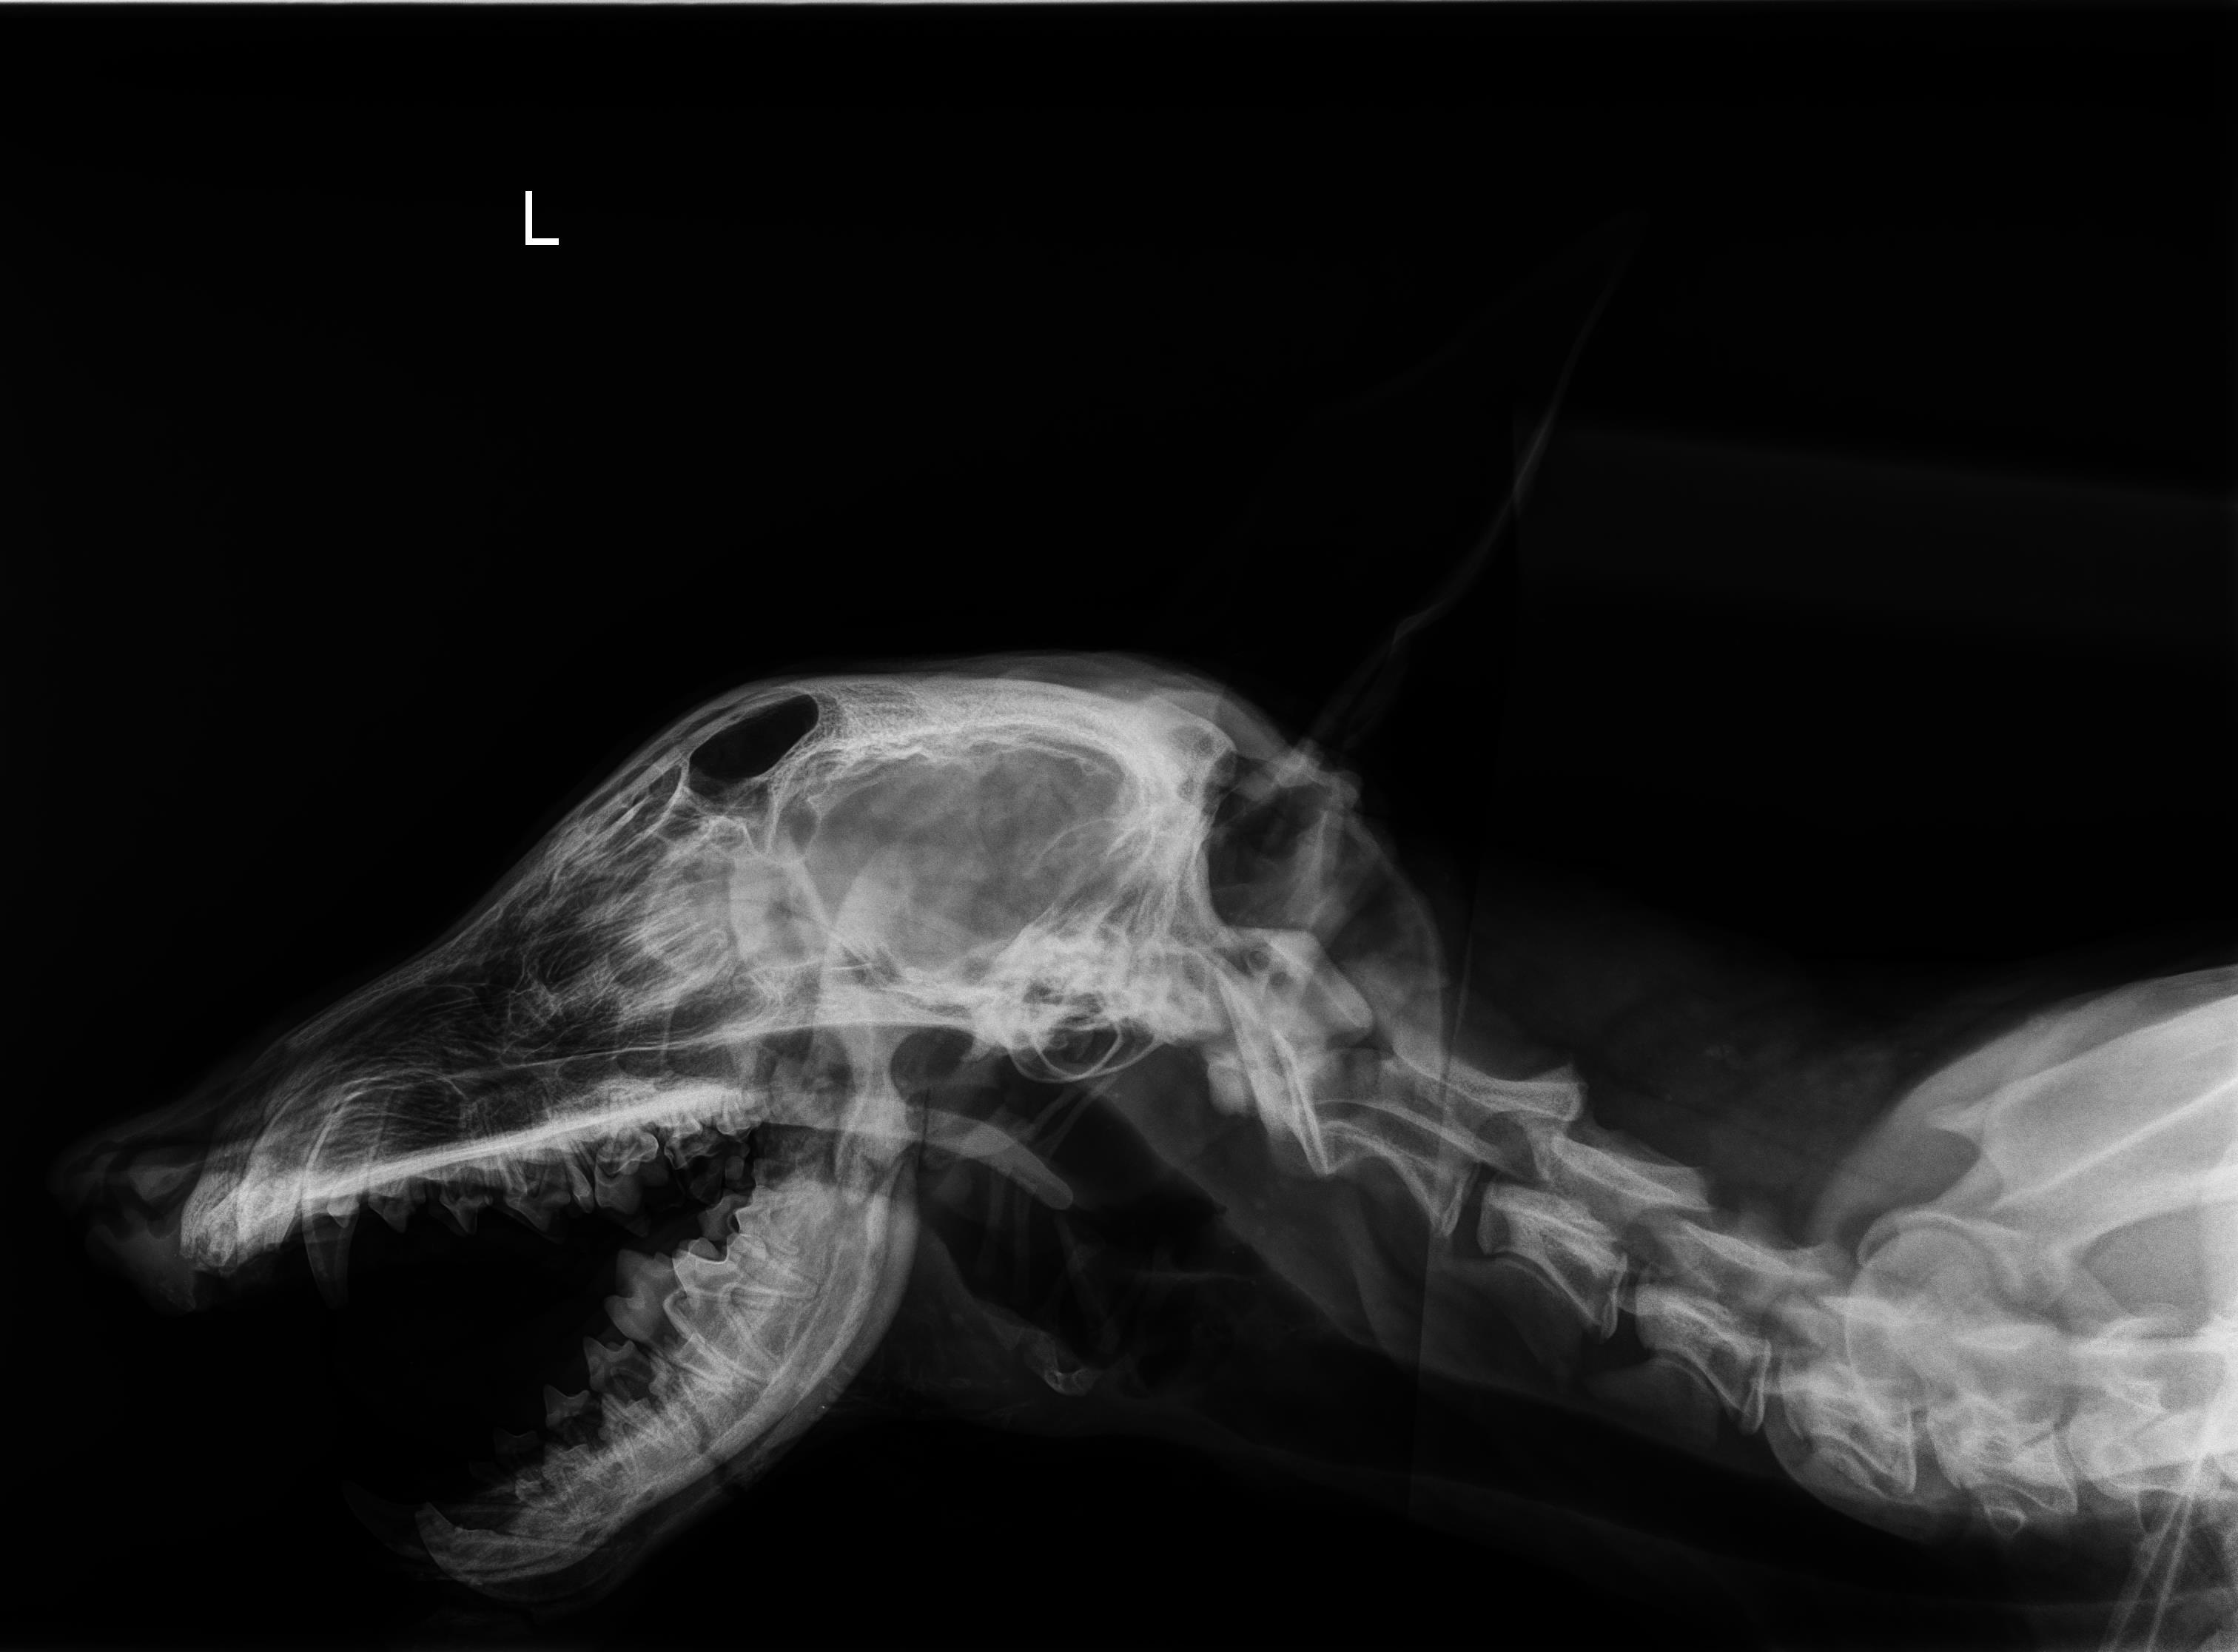

Es stellte sich heraus, dass die Verletzung entweder durch einen heftigen Autounfall oder eine Beißerei unter den Hunden dort entstanden sein muss. Der Kieferknochen auf der linken Seite ist an 3 Stellen gebrochen und fehlt stellenweise, zudem hat Iason kaum noch Zähne. Zu fressen muss für ihn die größte Qual gewesen sein, zudem kann man sich kaum vorstellen, wie groß die Schmerzen für ihn in diesem Zustand generell sein müssen...

Der gesamte junge Körper ist förmlich vom Schmerz gezeichnet, der Blick von ihm leer und ohne Leben, Iason wiegt gerade einmal 1/4 von dem, was ein gesunder Rüde in seinem Alter auf die Waage bringen müsste. Stathis, unser Tierarzt, hat ihn gestern sofort das erste Mal operiert, und Iason ist stabil aus der Narkose wieder aufgewacht. Der zeitgleich durchgeführte Bluttest auf Mittelmeerkrankheiten zeigte keine positiven Titer und somit einen erfreulichen Befund, das fehlende Fell ist eine von der Demodex-Milbe verursachte Entzündung der Haut, aufgrund des sehr schlechten Immunsystems. In der Operation wurde der Kieferknochen von Iason wieder fixiert und teilweise ersetzt, in den nächsten Tagen darf er diesen nicht benutzen und wird daher nur künstlich durch eine Sonde ernährt. Wir hoffen und beten sehr, dass er all das packt und nicht aufgibt, wir werden alles mögliche daran setzen Iason zu helfen! Danach werden noch eine zweite und auch dritte OP notwendig sein, um die Kieferknoch nach und nach wieder aufzubauen. Selbstverständlich werden wir Sie weiterhin auf dem Laufenden halten, und würden uns zudem auch über eine Kostenbeteiligung in Form einer Tierpatenschaft oder für die OP & Nachbehandlung sehr freuen.